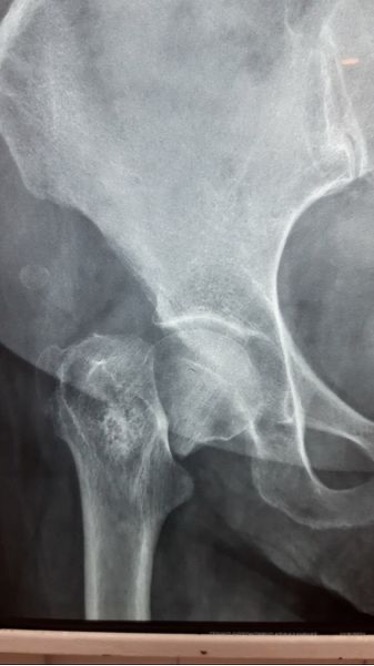

Ακτινογραφία πριν και μετά το παρεκτοπισμένο υποκεφαλικό κάταγμα ισχίου:

Κάταγμα αυχένα του μηριαίου οστού στο ισχίο σε γυναίκα ασθενή 60 ετών αρκετά παρεκτοπισμένο (Garden IV).